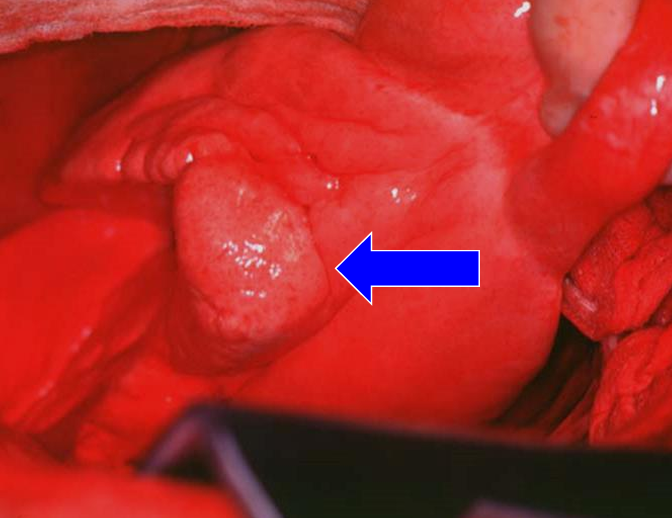

Whatโs your diagnosis?

- 3cm ์ด์์ด๋ฉด ์ ์ด๋ ๊ฐ๋ฅ์ฑ ํฌ๋ค๊ณ ๋ด

- Left caudal margin์ adenocarcinoma